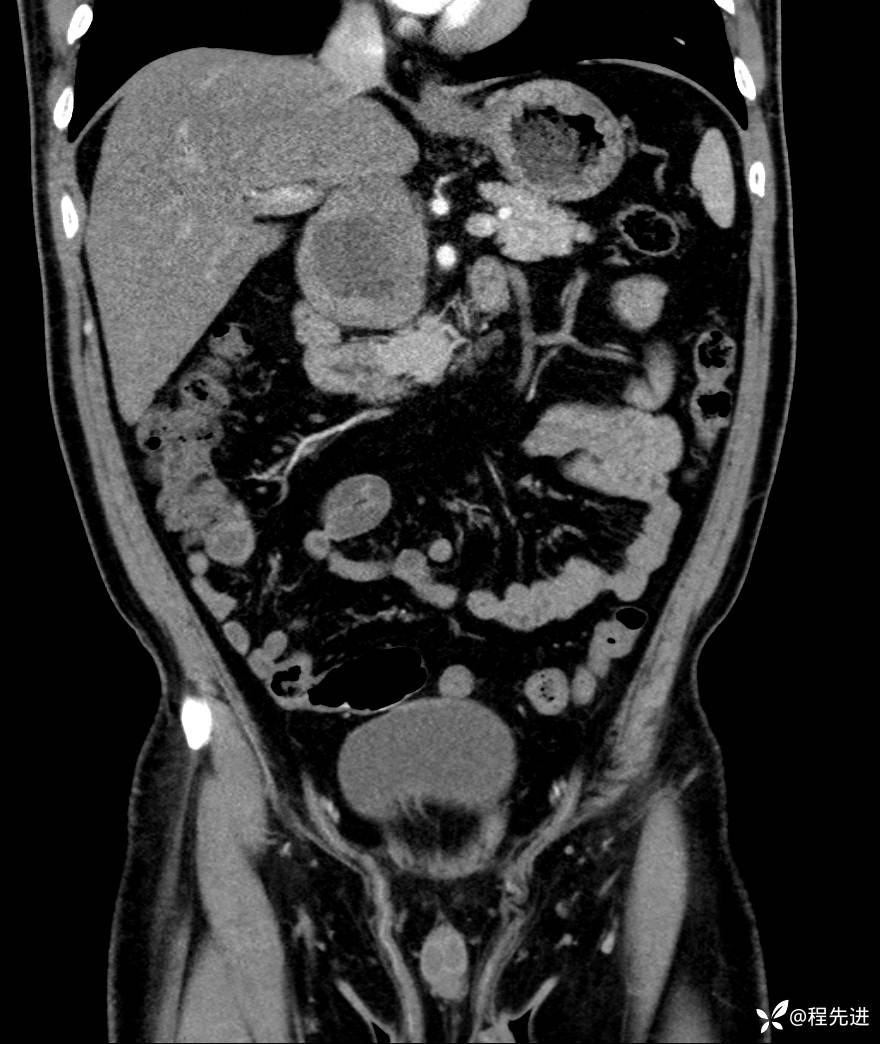

【腹盆】特别精彩病例|发现腹膜后肿物1月余

主诉:发现腹膜后肿物1月余

现病史:患者1月余前查体,行超声检查提示:后腹膜囊实性肿块;慢性胆囊炎伴胆囊内结石;无腹痛腹胀,不伴腹泻发热等;偶感腰背部酸痛。

CT平扫+增强: